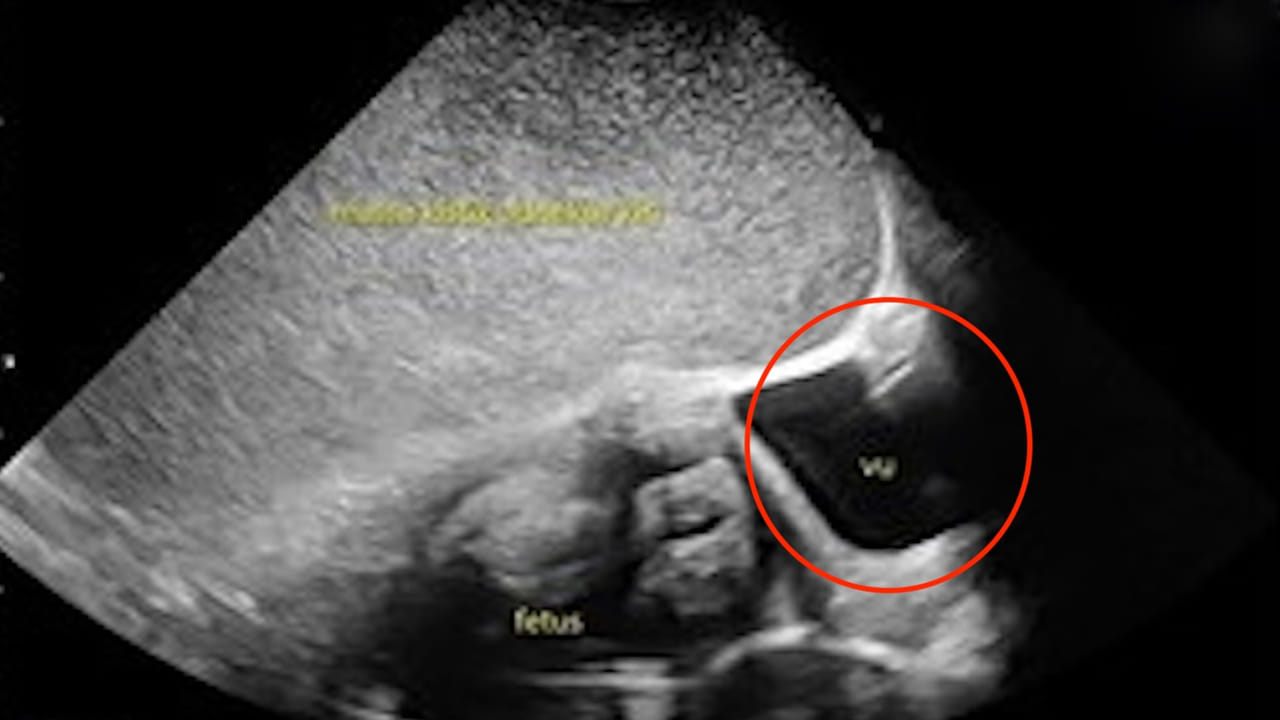

ఓ 26 ఏళ్ల గర్భవతిని హుటాహుటిన ఆస్పత్రికి తీసుకొచ్చారు ఆమె కుటుంబీకులు. తనకు కడుపునొప్పిగా ఉందని ఆమె చెప్పడంతో పురిటి నొప్పులేమో అని హాస్పిటల్ కు తీసుకెళ్లారు. ఇక అక్కడి వైద్యులు ఆమెకు ఎక్స్ రే తీయగా.. ఆమె కడుపులో పెరుగుతున్న పిండం చుట్టూ పెద్ద తిత్తి పెరుగుతున్నట్టు వైద్యులు గుర్తించారు. ఆమె ఆస్పత్రిలో అడ్మిట్ అయ్యేసరికి 34 వారాల గర్భవతిగా ఉంది.

ఆమెకు ఆరు వారాల క్రితం అల్ట్రాసౌండ్ స్కాన్ జరిగింది. అందులో అండాశయ తిత్తి ఉన్నట్లు గుర్తించారు. అది ఆమెకు 18వ వారంలో మాత్రమే కనబడింది. గర్భాశయంలోని ఒక భాగంలో పిండం పెరుగుతుండగా.. ఇంకో భాగాన్ని ఈ భారీ తిత్తి కప్పేసినట్టు డాక్టర్లు కనుగొన్నారు. అంతేకాకుండా దీని వల్ల శిశువు పెరుగుదల క్షీణించడం ప్రారంభమైందని వైద్యులు తేల్చారు. సరిగ్గా ఆమె ఆస్పత్రిలో అడ్మిట్ అయిన మూడు రోజులకు వైద్యులు శస్త్రచికిత్స నిర్వహించాడు. మొదటిగా 5 పౌండ్ల బరువున్న శిశువును ఎలాంటి ఇబ్బంది లేకుండా బయటకు తీయగా.. ఆ తర్వాత ఎడమ అండాశయాన్ని కప్పేసిన ఆ తిత్తిని తొలగించారు డాక్టర్లు. అందులో నుంచి 11 లీటర్ల ద్రవం వచ్చినట్టు తెలుస్తోంది. అలాగే ఇది 35 సెం.మీ వ్యాసం కలిగి ఉంది. ఇండోనేషియాలోని జకార్తాలో ఉన్న డాక్టర్ సిప్టో మంగున్కుసుమో ఆసుపత్రిలో చికిత్స పొందిన తల్లి ఆశ్చర్యకరంగా.. త్వరగా కోలుకుంది. ఎలాంటి సమస్యలు లేకుండా డిశ్చార్జ్ అయింది.